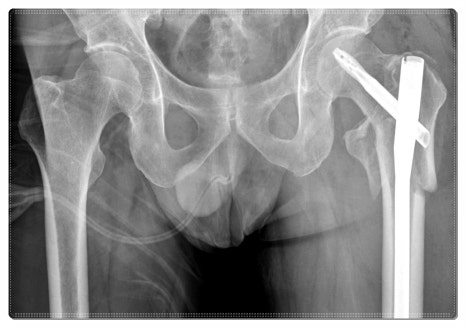

그래서 엑스레이 등을 통한 정밀 진단으로 현재 골격 상태를 확인하는 동시에,

한의학적 관점에서 골반의 균형을 바로잡는 부분도 함께 고려하게 됩니다.

수술 이후에도 다리가 뜻대로 움직이지 않거나, 비가 오기 전후로 쑤시는 통증이 반복된다면

이제는 단순한 휴식이 아니라 체계적인 치료를 고민해보셔야 할 시점일 수 있습니다.

보행 자세가 이전과 달라졌다고 느끼거나, 한쪽 골반이 유독 튀어나온 느낌이 든다면

이미 골반 정렬이 흐트러졌을 가능성도 있습니다.

이 경우 근육의 긴장을 완화하고 관절의 위치를 바로잡는 한방 통합 재활 치료가 도움이 될 수 있습니다.